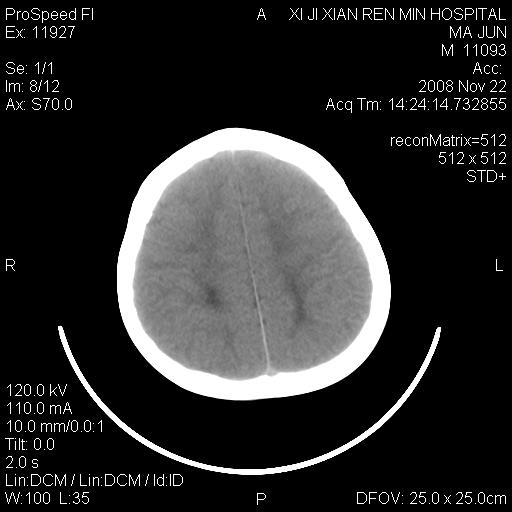

双侧侧脑室前角,三角区旁及半卵圆中心区白质呈低密度改变,半卵圆中心区病灶呈片状融合趋势,无软化征像,脑室无扩张,各神经核团无异常改变,脑皮质无萎缩等征像,结合病史考虑髓鞘发育不良性脑白质病,异染性脑白质营养不良可能性大.不除外多发性硬化等其他改变,建议磁共振检查

脑白质减少,双侧侧脑室额角旁及半卵圆中心可见对称性略低密度影,边缘尚清,考虑脑白质发育不良